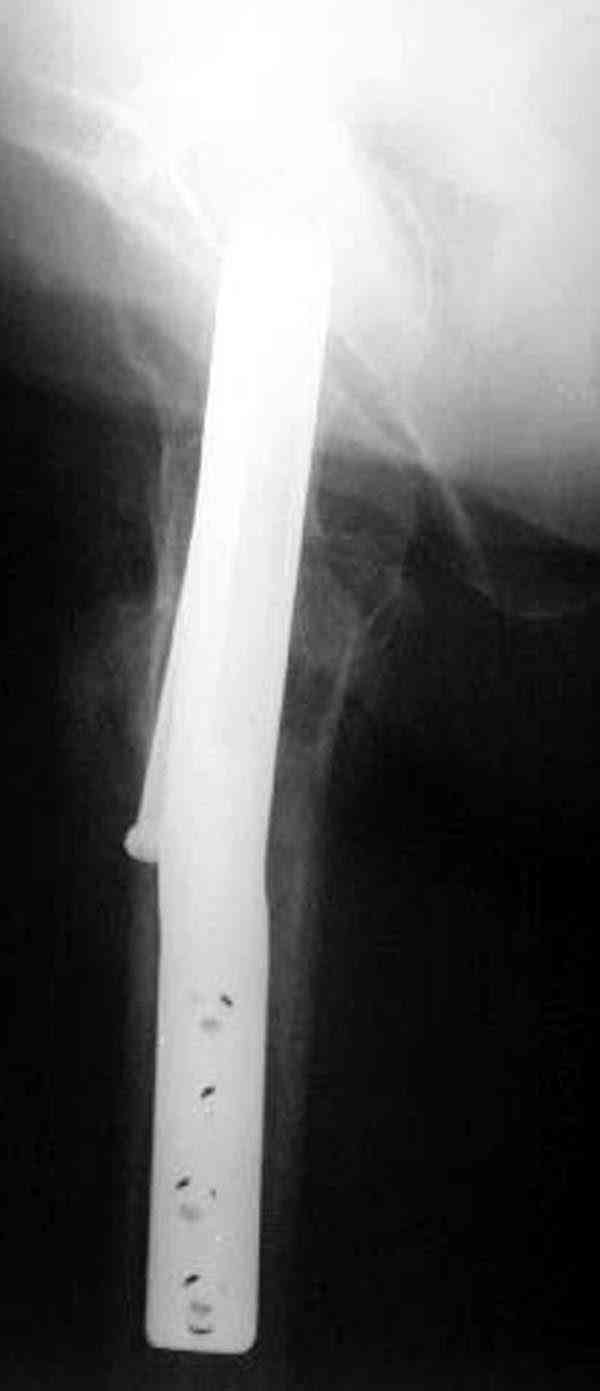

Уважаемый Антон! У меня было всего три клинических наблюдения, снимки были продемонстрированы на московской конференции. Количества этих снимков хватило для подачи заявки, а затем и получения патента на изобретение. В свое время РОСПАТЕНТ потребовал подтверждения методики клиническими наблюдениями. У одной из больных действительно произошла повторная травма, и произошел подвертельный перелом на стороне армированной шейки бедренной кости (см. снимки). Это подтвердило основную идею изобретения - была сохранена и головка, и армированная шейка бедренной кости. Но тут не обошлось безпроблем. Анестезиологи отказались давать наркоз, а провести остеосинтез под м/а пластиной и винтом DHS не согласилась больная. Дальнейшее лечение скелетным вытяжением. На контр. Рентгенограмме через 2 месяца признаки формирования костной мозоли. Повторных обращений двух других пациентов не было. Для более детальных исследований и выводов необходимо значительно большее количество клинических наблюдений. Такие исследования могли быть проведены в условиях клиник медуниверситета. Напомню, я работаю в травмотделении провинциальной городской больницы. Насчет экспертов страховых компаний, так пусть они выскажут свое мнение. Армирование кости - это плановые операции по желанию больного, какие здесь могут быть противоречия? На армирование все больные, к моему удивлению, согласились довольно легко и сразу, поэтому остеосинтез и армирование были проведены в течение одной операции. С уважением А.М.

Кстати говоря, ослабление латерального кортекса винтом может способствовать возникновению вертельного и подвертельного перелома.

Коллега Челноков прав, здесь еще имеется риск перелома за счет ослабления латерального кортекса. Во время установки канюлированных шурупов за редким исключением спица вводится с одного раза, множественные попытки ослабляют латеральный кортекс, что станет источником перелома в этом месте.

Здесь случай перелома из-за ослабления латерального кортекса через 3 недели после операции на шейке. Шурупы были установлены под большим углом, слабый латеральный кортекс не выдержал нагрузку.